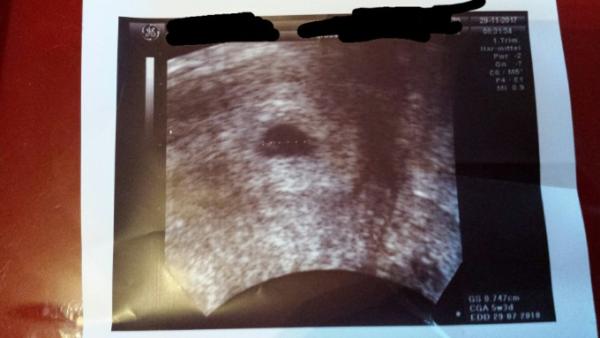

Hallo, Ich komme gerade vom Doc, und wurde auf 5+3 datiert, mit ET 29.07. Also doch früherer Eisprung, so wie ich es vermutet habe. Dann mache ich es mir mal hier bei euch bequem Habe auch schon das erste Bildchen bekommen mit Fruchthöhle und Dottersack. Den nächsten Termin hab ich nächsten Mittwoch dann hoffentlich mit

Bild zu es wird ein Juli-Kind :) - Forum für Juli - Mamis